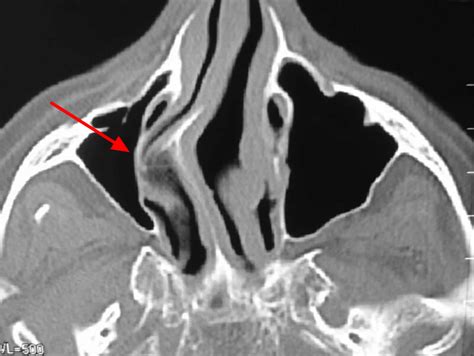

Diagnosing a deviated septum nose typically involves a physical examination and a review of your medical history. Your healthcare provider may use various diagnostic tools to assess the severity of the deviation. These tools can include:

• Imaging tests: X-rays, CT scans, or MRI scans may be used to get a detailed view of the nasal structure.